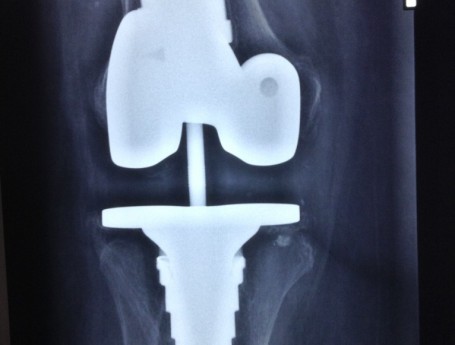

Revision Total Knee Replacement After a fructure

• Revision Total Knee Replacement After a fructure